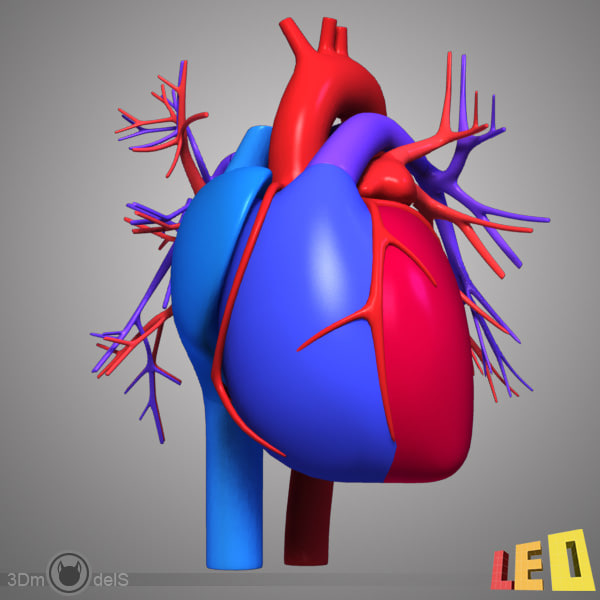

Human Heart Drawing Outline at GetDrawings | Free download  3d anatomy human heart

3d anatomy human heart  Show me a diagram of the human heart? Here are a bunch! - Interactive Biology, with Leslie Samuel

Human Heart Sketchbook study by bluesytealyren on DeviantArt | Human heart drawing, Anatomical  3d human heart

3d human heart  Animated Realistic Human Heart - Medically 3D asset

Animated Realistic Human Heart - Medically 3D asset  Zygote::3D Heart Model | Medically Accurate | Human Anatomy

Zygote::3D Heart Model | Medically Accurate | Human Anatomy  Zygote::Solid 3D Human Heart Model

Zygote::Solid 3D Human Heart Model  3D human heart anatomy model - TurboSquid 1283134

3D human heart anatomy model - TurboSquid 1283134  anatomy human heart 3d c4d

anatomy human heart 3d c4d  Modeled human heart section 3D model - TurboSquid 1657004

Modeled human heart section 3D model - TurboSquid 1657004  Heart by Rustamova on @DeviantArt | Anatomical heart art, Anatomy art, Heart drawing

Heart by Rustamova on @DeviantArt | Anatomical heart art, Anatomy art, Heart drawing  3d human heart

3d human heart  3d human heart

3d human heart  3d human heart anatomy model

3d human heart anatomy model  //thebrainstormlab.com/banners/ami_banner.jpgThis is a medical | Heart anatomy drawing, Human

//thebrainstormlab.com/banners/ami_banner.jpgThis is a medical | Heart anatomy drawing, Human  Human Heart Section 3D model | CGTrader

Human Heart Section 3D model | CGTrader  human heart - internal anatomy 3d model

human heart - internal anatomy 3d model  3D Illustration Human Heart 3D Images - Iwish Iwas

3D Illustration Human Heart 3D Images - Iwish Iwas  Realistic Human Heart Drawing at GetDrawings | Free download

Heart Anatomy Human Heart Images Hd 3D - Dreaming Arcadia  Anatomical Heart Drawing at GetDrawings | Free download

Detailed 3D Human Heart | CGTrader  3d human heart

3d human heart  Realistic detailed 3d human anatomy heart Vector Image

Realistic detailed 3d human anatomy heart Vector Image  3D human heart model - TurboSquid 1149348

3D human heart model - TurboSquid 1149348  Get Easy Pencil Heart Art Easy Pencil Heart 3D Drawing Gif â Drawing 3D Easy

Human Heart Anatomy 1 3D model | CGTrader  How to draw realistic human heart||3d human heart sketch

3D Human Heart animated | CGTrader  How the Human Heart Works | Safety and Health Solutions

3d human heart  Human Heart Study Drawing, HD Png Download - kindpng

3D dissected human heart model - TurboSquid 1361664  10 Realistic Heart Drawings and Tattoos â Simple Human Heart Sketch for 2022 | Do It Before Me

Heart Anatomy Human Heart Images Hd 3D - Dreaming Arcadia  Realistic Human Heart 3D model | CGTrader

Realistic Human Heart 3D model | CGTrader  anatomy human heart 3d c4d

anatomy human heart 3d c4d  Human Heart Section 3D model | CGTrader

Human Heart Section 3D model | CGTrader  3d human heart

3d human heart  Royalty Free Human Heart Clip Art, Vector Images & Illustrations - iStock

Human Heart Cutaway Anatomy 3D model section | CGTrader  Human Heart by Mutantenmaid on DeviantArt

3D human heart - TurboSquid 1737445  How to Draw a Human Heart - Really Easy Drawing Tutorial

human heart interior 3d model  Image of Human Heart 3D Illustration | Stock Image MXI28575

Image of Human Heart 3D Illustration | Stock Image MXI28575  The human heart by SkarlettFury on DeviantArt | Human heart drawing, Heart drawing, Heart art

Human Heart Anatomy 1 3D model | CGTrader  human heart anatomy 3d max

human heart anatomy 3d max  Heart Anatomy Human Heart Images Hd 3D - Dreaming Arcadia

Heart Anatomy Human Heart Images Hd 3D - Dreaming Arcadia  Pin on Body Parts Drawings

3d model heart anatomy  3d human heart anatomy model

3d human heart anatomy model  3d human heart section

3d human heart section  human heart solidworks 3d model

human heart solidworks 3d model  Human heart by kortney16 on DeviantArt

human heart - internal anatomy 3d model  Heart Diagram Human Heart Images Hd 3D - img-Badr

Heart Diagram Human Heart Images Hd 3D - img-Badr  Real Human Heart Drawing at GetDrawings | Free download

3d Human Heart On Abstract Background Stock Illustration 635691020